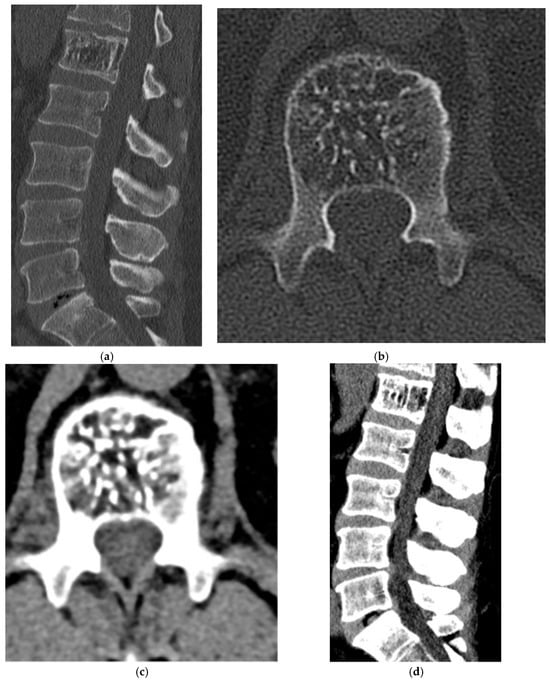

Paget’s Disease